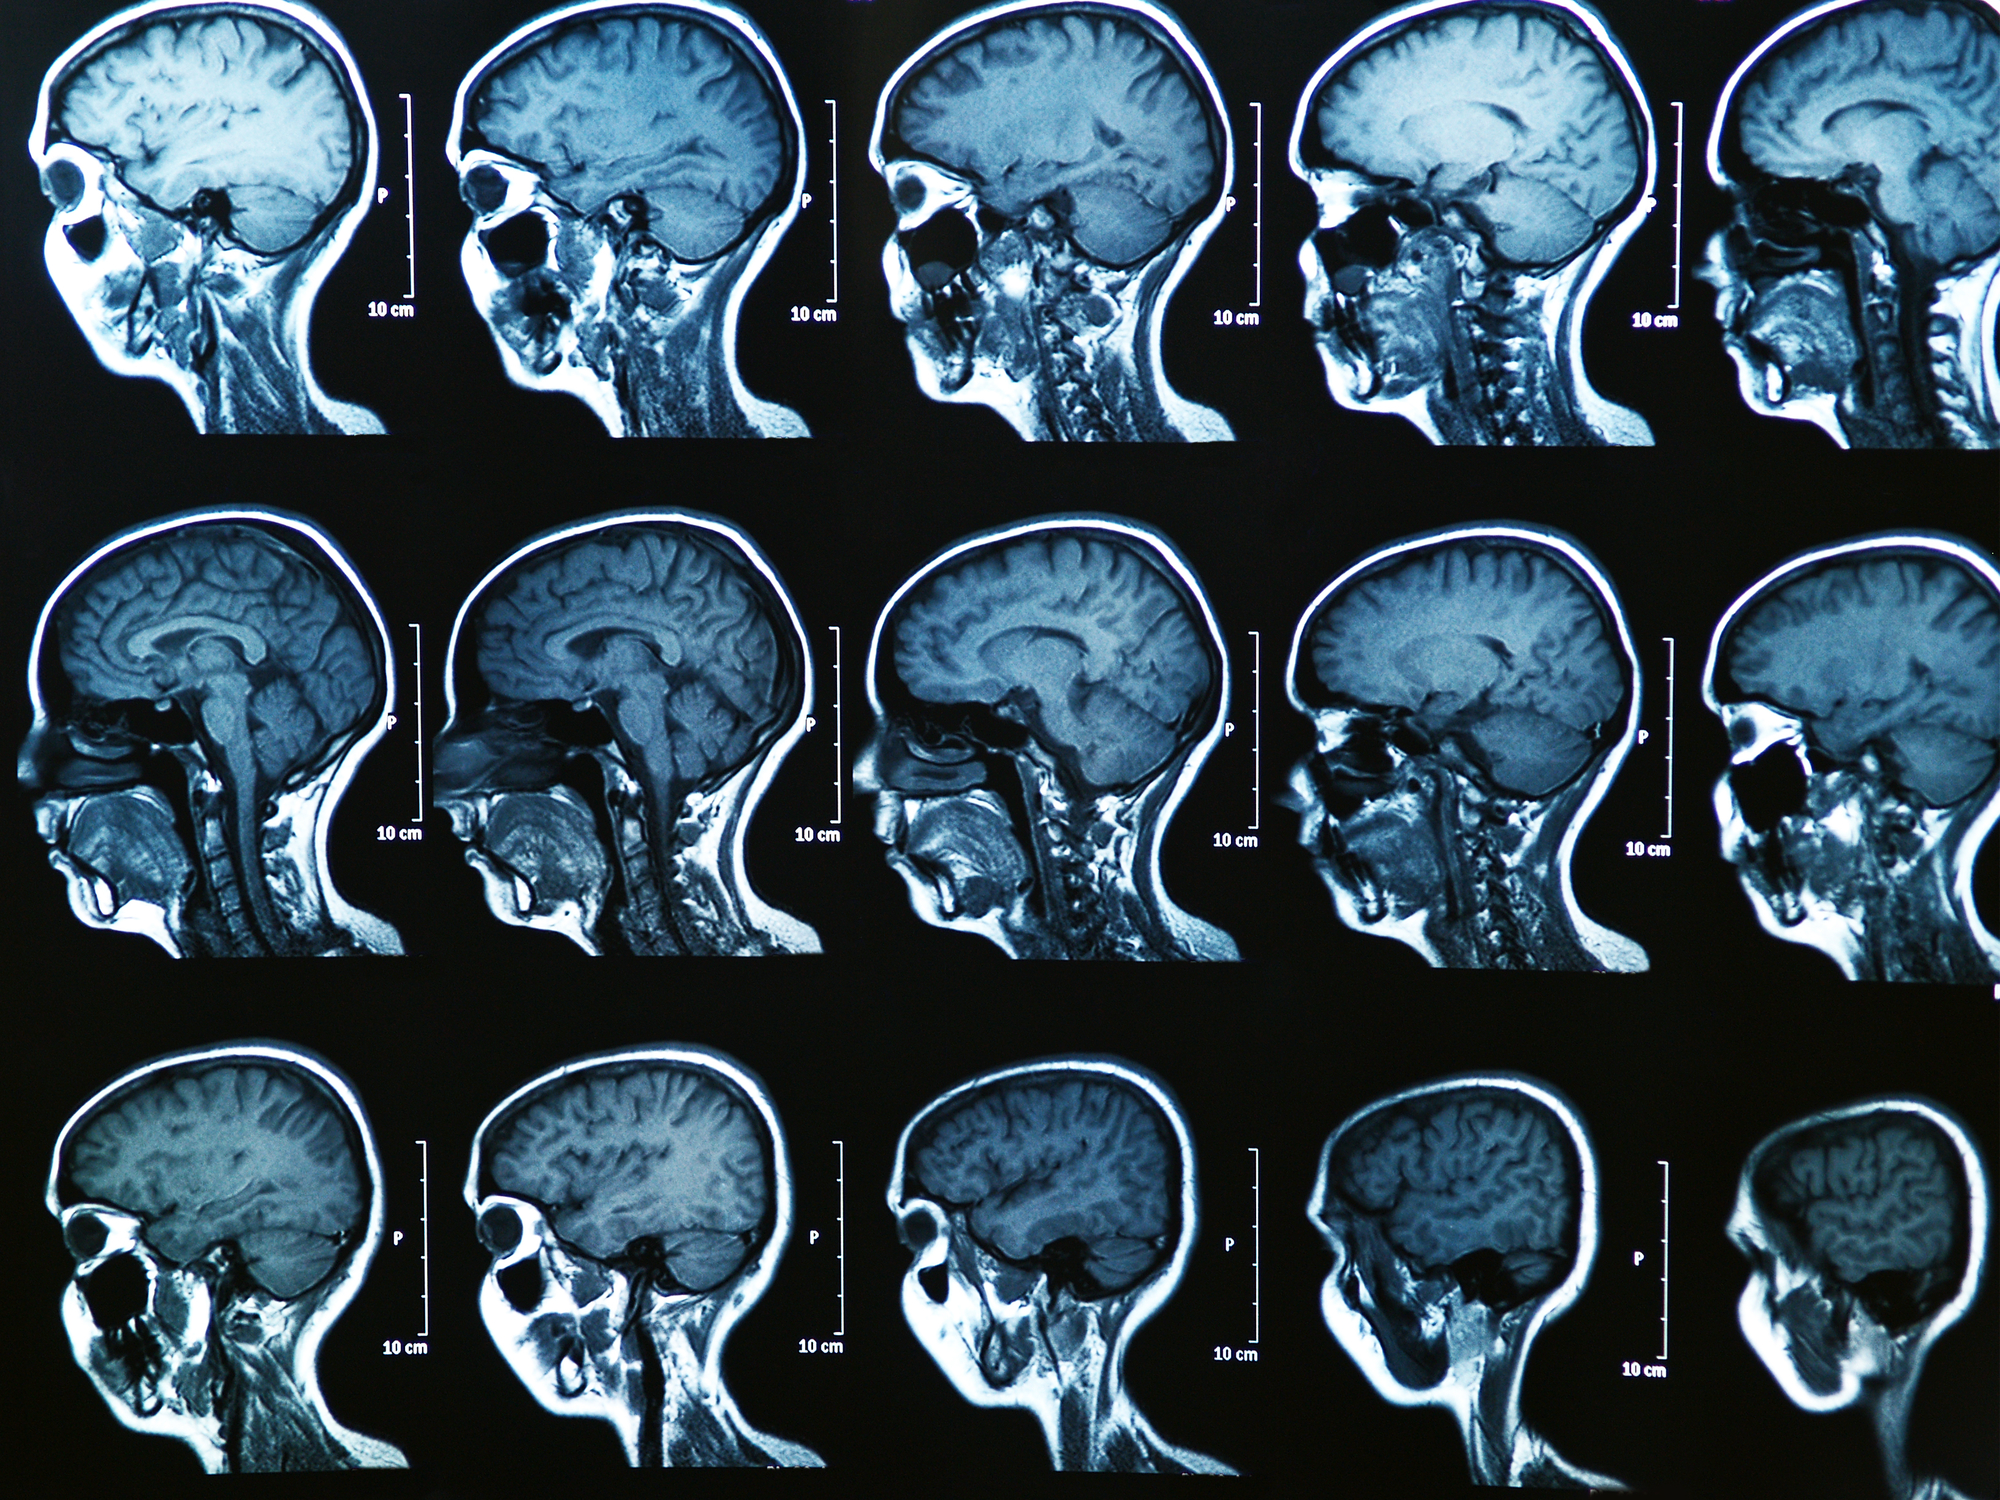

Three months after concussion, the brains of adolescent hockey players still don’t look normal Deposit Photos

But a new study shows that even when young hockey players who suffer concussions appear fully recovered, and doctors and trainers return them to the ice, scans still show abnormalities in the brain. The findings were published today in the journal Neurology, and add to a growing number of studies showing that neurological changes linger even after clinical symptoms of a concussion clear up. Athletes may appear back to normal on a battery of cognitive and physical tests, but not on an MRI scan.

Menon’s study followed a group of male hockey players, aged 11 to 14. Fourteen players suffered a concussion during the season, and went through a functional MRI scan, cognitive, memory and balance test both one to three days after the injury and again three months later. Their tests were compared with those of 26 injury-free players, who served as controls.

On average, the injured kids took 24 days to return to play, and they were all back in the game by the time the three month mark rolled around. At that point, they tested normally on the cognitive, memory and balance tests—but they still had changes to some structures in the brain and changes to the connectivity patterns between brain regions. The types of abnormalities are consistent with those seen in previous studies done in other, older populations, Menon says, but it’s a particular concern for young athletes, whose brains are still developing.